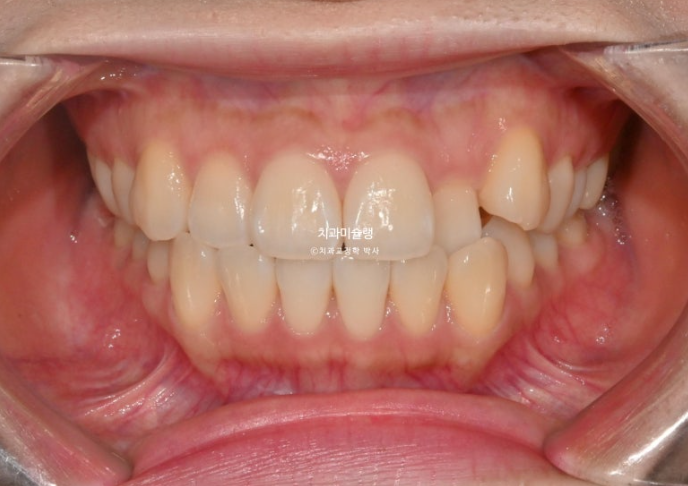

중심선 불일치, 덧니, 측절치 반대교합을 인비절라인 라이트로 치료한 증례입니다.

중심선 불일치, 덧니, 반대교합 등이 보입니다.

절단교합도 보이고

앞니쪽은 뒤죽박죽이나 그에 비하면 어금니 교합은 아름다운 1급 교합관계를 보입니다.